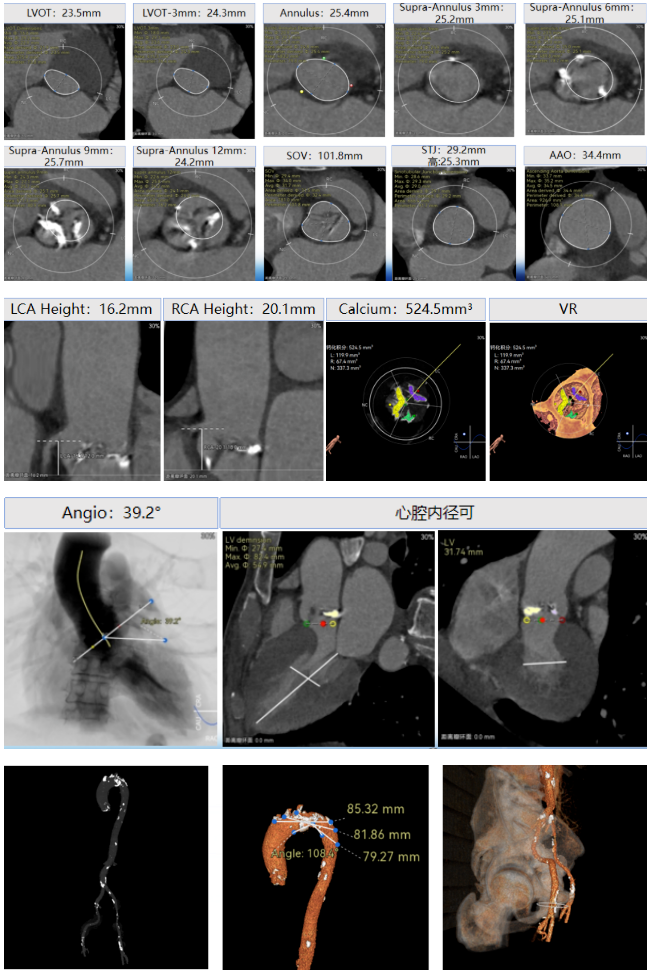

周达新教授 复旦大学附属中山医院 共识引路,干瓣启新,共赴临床解决方案:当前,结构性心脏病的介入治疗已迈入微创化、精准化的新时代。技术的革新、创新器械的上市,都是我们中国技术领跑的印证,《专家共识》的应运而生是中国医生对于行业“规范化”的践行,让治疗更精准、让医者更贴近“以患者为中心”的医疗本质。 潘文志教授 复旦大学附属中山医院 严谨求真重思考 创新临床互验证:在医学的漫长征途中,新器械的突破与严谨的临床研究是两大核心驱动力。拥抱创新的同时需要严谨求证,预装干瓣作为创新器械,其即取即用的特性可以很好的适配“急诊”的场景,此外,国产创新不是简单的复制,干瓣的瓣叶质地不是字面意思“干”的,而具“曲柔性”。所以,需要多看多测,才能全面了解一款产品。《经导管心脏瓣膜治疗术》的问世也是凝结着我们带着临床思维思考的结晶的“独家秘笈”,希望能够将“来时的路”变成未来行业同行者的“高效学习之路”! 患者病史 多病共存陷困境,主动脉瓣狭窄成 “首要威胁” 现病史:患者反复活动后胸闷2年余,无胸痛、心悸,无头晕、晕厥等不适,未予重视。患者轻微体力活动(快走、爬楼梯)即胸闷气促,静息及夜间无不适,无咳嗽、心悸等症状。为进一步诊疗收入我科,患病以来精神、食欲、睡眠、二便及体重均正常。 既往史: 2025年5月7日因小便不畅至外院住院病理穿刺确诊前列腺癌,期间检查心超提示主动脉瓣钙化伴重度狭窄,遂暂缓前列腺手术。2025年05月30日至我院就诊。 2025年5月20日开始服用比卡鲁胺片。患者血脂异常,长期服用丹参滴丸,麝香保心丸,心通颗拉。 手术史外伤史:10年前行肺手术,具体不详。否认外伤史。 入院检查 心电图提示:窦性心动过缓;ST-T改变; 心超显示:主动脉瓣钙化伴重度狭窄及轻度反流,Vmax 4.8m/s、PGmax 93mmHg、PGmean 47mmHg;左房增大,左室壁增厚。 冠状动脉CT造影:左前降支中段浅表心肌桥,主动脉瓣增厚伴重度钙化,主动脉粥样硬化。 术前CT 三叶瓣,中度钙化,主动脉根部直径25.4mm,LVOT直径23.5mm 双侧冠脉开口高度尚可,瓦氏窦尚可,ST尚可,升主尚可,冠脉风险小;中度钙化,心脏角度39.2°;心腔内径可,左室壁增厚。 外周走行尚可,全主动脉存在散在钙化,右侧穿刺点需避开钙化,血管内径可,血管内壁存在纤维增厚。 手术策略:右侧股动脉为主入路,使用20F大鞘;20球囊预扩,植入AV29瓣膜; 手术过程 主动脉根部造影 输送系统柔顺过弓 定位 缓慢释放瓣膜 造影观察 稳定脱钩 最终造影性钙位置良好,轻微瓣周漏 术后超声:轻度瓣周漏,术后平均压差11mmHg 出院前超声:平均压差11mmHg 在多基础疾病患者日益增多的当下,该病例也为临床提供重要启示:针对合并肿瘤、既往手术史的复杂瓣膜病患者,需通过多学科协作(心内科、肿瘤科、麻醉科等)全面评估病情,结合精准影像技术与适配器械,制定个体化手术方案,才能在保障安全的同时,实现最优疗效。 作为中国结构性心脏病领域的标杆学术活动,中国结构周 2025为这类高水平临床病例提供了交流平台,助力推动我国结构性心脏病诊疗技术持续创新,让更多复杂瓣膜病患者受益于精准医疗方案。 ProStyle A®预装干瓣——助力临床最优化解决方案: 轻松过弓,精准可控:该病例全主动脉存在散在钙化,右侧穿刺点需避开钙化,ProStyle A®较细的尺寸+柔顺的输送系统通过性能得到了很好的验证; 平稳释放:平衡的径向支撑力降低了释放过程中的张力,流入端小锥角设计能够迅速锚定贴边; 预装干瓣 便捷顺安:金仕生物专利抗钙化技术运用纳米技术去除组织内的细胞碎片和磷脂,封闭游离醛基,从根本上阻断了瓣膜钙化的多项因素,显著提升了瓣膜的耐久性;同时,相比较传统戊二醛保存方式,干式存储最大限度的保留心包的亲水亲油平衡,还原组织天然曲柔性,进一步保障了瓣叶开合,保证长期耐久性; 专家简介 葛均波 复旦大学附属中山医院(点击查看专家详细简历) 周达新 复旦大学附属中山医院(点击查看专家详细简历) 潘文志 复旦大学附属中山医院(点击查看专家详细简历) · END ·